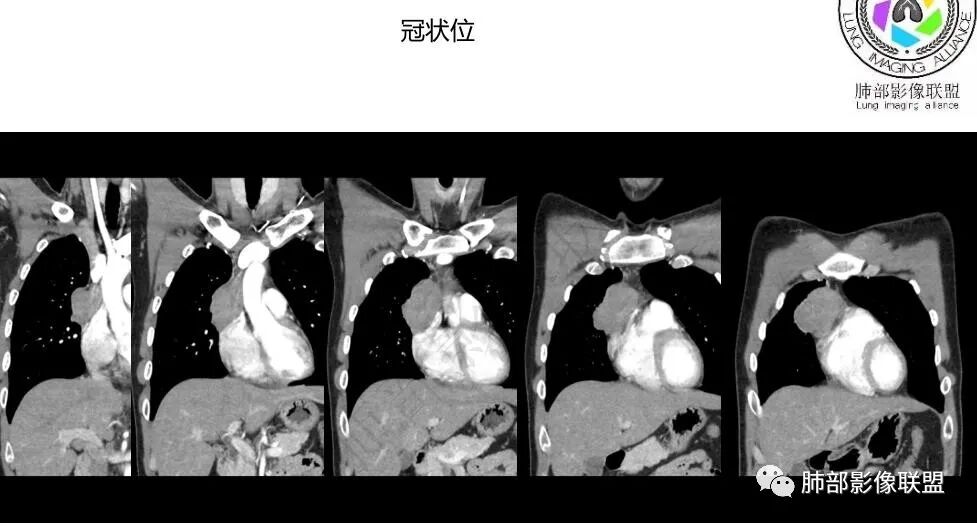

前纵隔右侧见大肿块,边缘清,同侧内乳动脉增粗,渐进性延迟强化明显,强化密度不均匀,中心见偏低密度灶,上腔静脉内后侧推压移位(提示肿块质地偏硬),副神经节瘤,与巨淋巴细胞增生症鉴别。

青年男性,咳嗽,右上前纵隔不规则肿块,分叶,上腔静脉受压,内乳动脉增粗,延迟强化明显,坏死不明显,考虑来源纵隔,胸腺瘤,淋巴瘤,神经源性肿瘤都可以,比较年轻,猜个淋巴瘤吧。神经源性肿瘤代排。

青年男性,前纵隔偏右侧肿块,分叶,与邻近血管分界不清,上腔静脉受压,不均匀渐进强化,点状坏死,考虑胸腺瘤,鉴别胸腺类癌

前纵隔右侧不规则软组织肿块,边缘欠清,增强渐进性强化,内见星状无强化分隔,部分分隔延迟强化,青年男性,首先考虑精原细胞瘤,鉴别胸腺瘤,NSE轻度升高,类癌也需鉴别!

前纵隔肿块,轻度分叶,边界不清楚,延迟强化,可见分隔,倾向恶性或具有一定侵袭性病灶。

一.精原细胞瘤  20-40岁 ,年轻男性多见,密度均匀,边界清楚,轻度强化,可有坏死,基本不出现钙化,HCG可升高,AFP一般不升高,侵犯血管的程度一般比淋巴瘤明显。

二.纵隔淋巴瘤 青少年(20-30)老年(60-80)两个高峰年龄段,男性略多。软组织肿块,常有多结节融合感,边缘较光整,少见分叶。跨间隙,跨中线生长,常见周围淋巴结影,治疗前较少钙化,少见胸膜及心包结节。淋巴瘤常往血管间隙生长,包绕临近大血管,而血管受侵犯较轻,多为轻中度强化,幅度大于30Hu。

三.高危型胸腺瘤 年龄偏大,以中老年多见,中度或明显强化,强化幅度大于淋巴瘤,有囊变和坏死,可见钙化,胸膜转移,三分之一有重症肌无力,尤其是B2-B3型等。胸腺癌可见淋巴结转移。